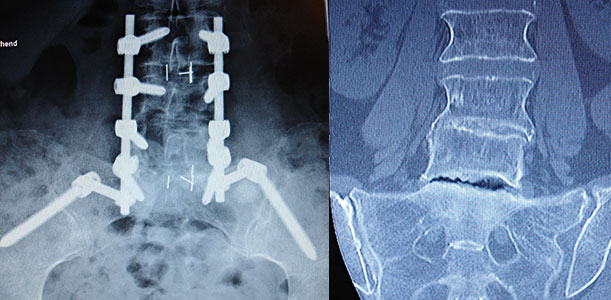

Wenn das SI-Gelenk und die LWS operiert werden müssen, kann neben der LWS-Versteifung zusätzlich eine Versteifung des SI-Gelenks erfolgen.

Wenn das SI-Gelenk und die LWS operiert werden müssen, kann neben der LWS-Versteifung zusätzlich eine Versteifung des SI-Gelenks in der beschriebenen Ausräumung vom Recessus und Knochenanlagerung erfolgen. In diesem Fall wird aber eine Verschraubung der LWS auf den Beckenkamm (Iliumschraube) durchgeführt, wodurch die Überbrückung erfolgt (siehe Fotos). n